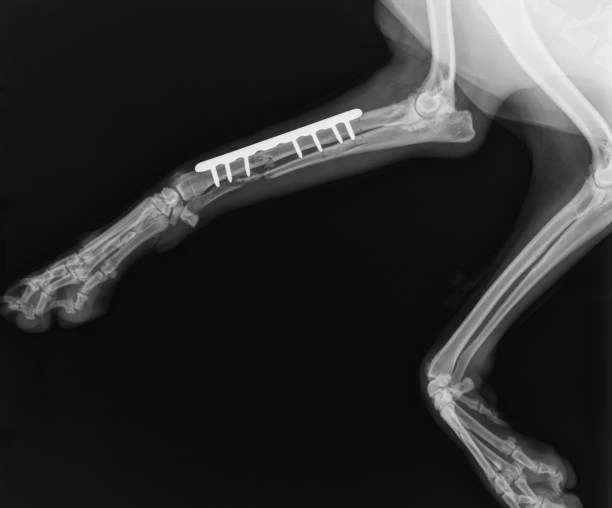

A realização do raio x para animais em sumaré é um dos procedimentos fundamentais dentro da clínica veterinária, permitindo aos profissionais identificar possíveis problemas de saúde nos animais de forma rápida e precisa.

O serviço de raio x para animais em sumaré oferecido pela RaçãoPet Saúde Animal é essencial para diagnosticar diversas condições, como fraturas ósseas, problemas cardíacos, obstruções intestinais, entre outros.

Os exames de imagem, como o raio x para animais em sumaré, são realizados de forma rápida e segura na clínica veterinária, garantindo conforto e tranquilidade aos animais durante o procedimento.